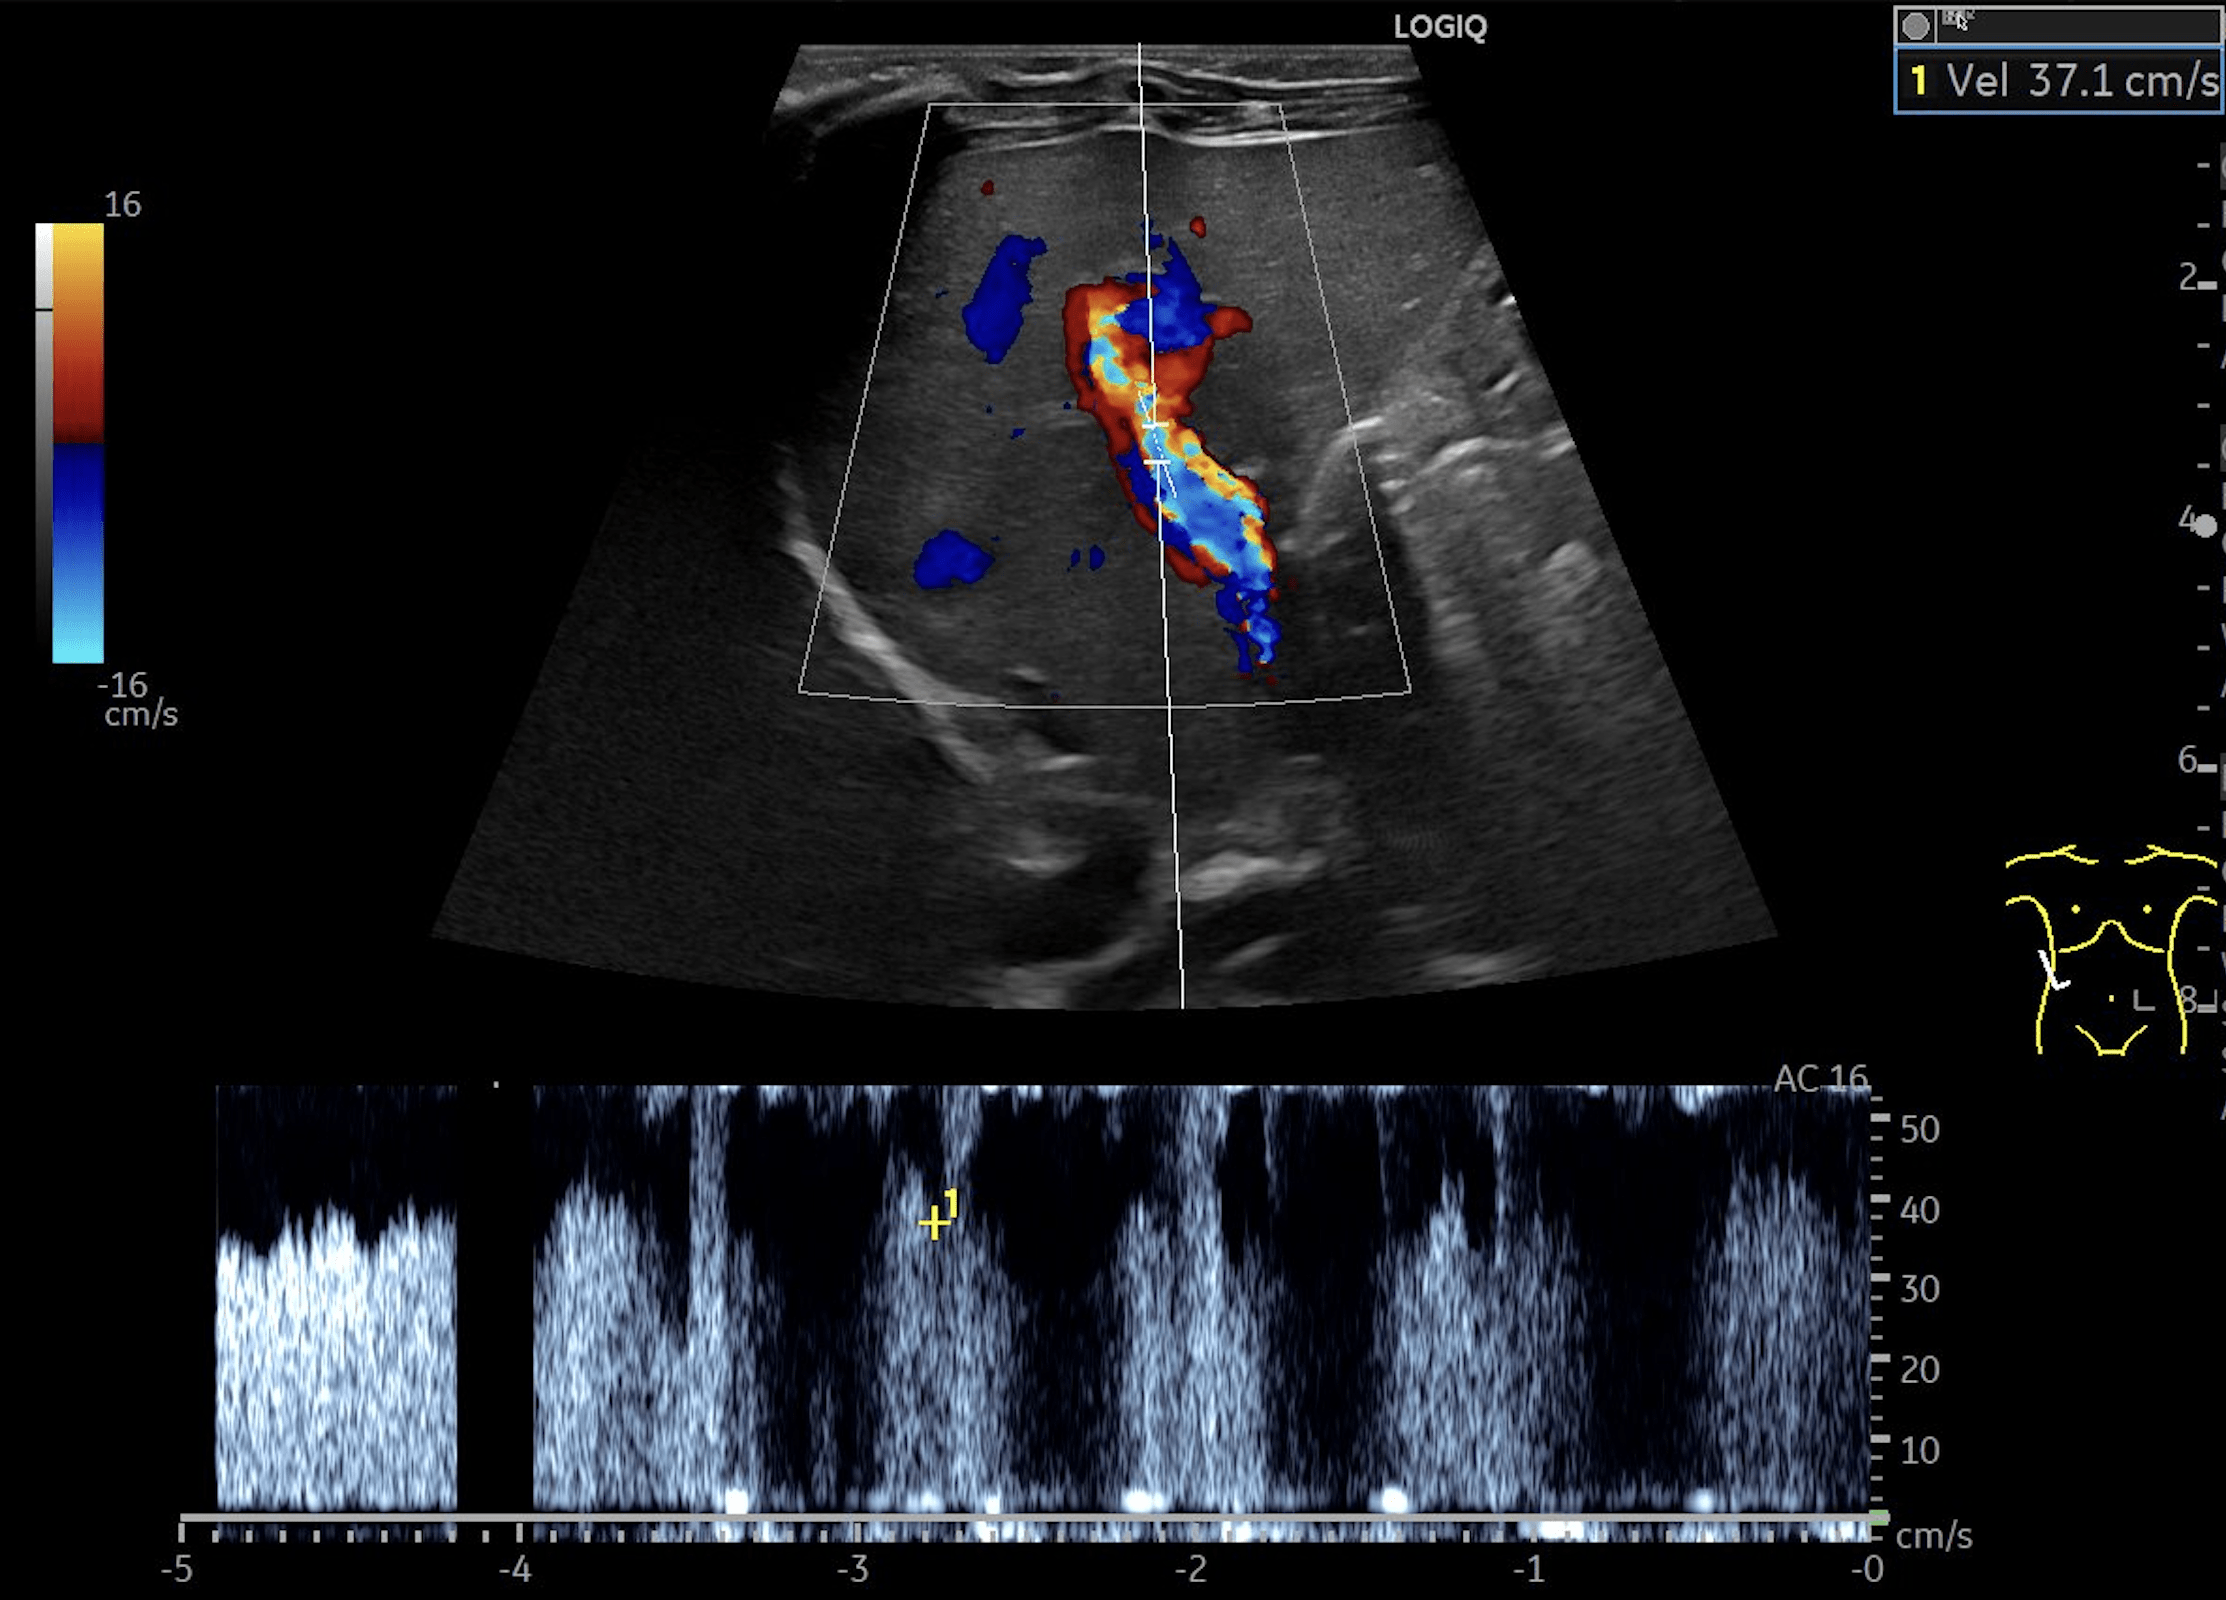

C: Triplex Doppler image of the portal vein demonstrating flow velocities of approximately 37cm/s.

Multiple hepatic lesions were identified on ultrasound (A). Some lesions appeared as typical, well-defined hyperechoic cavernous hemangiomas (2), while others demonstrated large, tortuous vessels. Additional lesions showed a hyperechoic rim with a hypoechoic center and internal Doppler flow, consistent with capillary hemangiomas (2). In some HH (B), arteriovenous shunting was suspected. However, Triplex Doppler examination demonstrated normal hepatoportal flow in the portal vein (C) with flow velocities below 40 cm/s – within the normal range for the age – as well as a normal triphasic flow pattern in the hepatic veins (D).